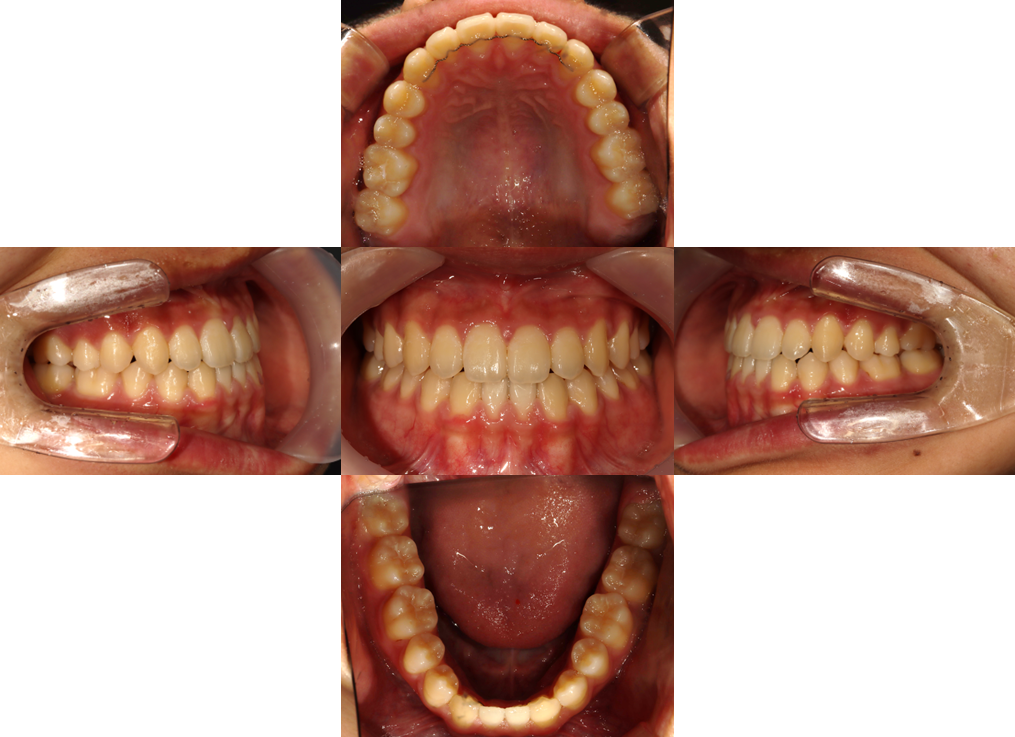

전체 교정 치료 #3

작성자

최고관리자

조회

715

작성일

23-07-13